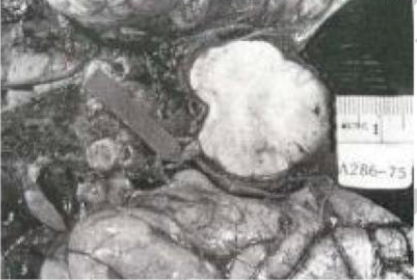

Apa yang ditunjukkan oleh spesimen kasar di bawah ini

A. Sklerosis Majemuk

B. Kern Ikterus

C. Nekrosis Laminar

D. Zat abu Heterotopic

E. emboli Lemak

C